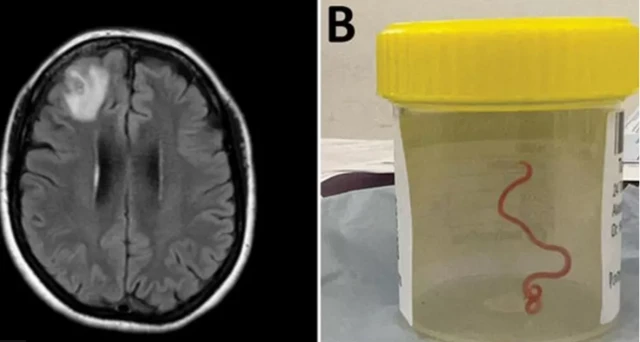

વૈજ્ઞાનિકોનું કહેવું છે કે તેમને એક મહિલાના મગજમાંથી 8 સેન્ટિમીટર લાંબો જીવતો કૃમિ મળી આવ્યો છે. વિશ્વમાં આ પ્રકારની આ પ્રથમ ઘટના છે.

કૅનબરામાં ગયા વર્ષે એક સર્જરી દરમિયાન ઑસ્ટ્રેલિયન મહિલાના મગજના આગળના ભાગમાંથી દોરી જેવું દેખાતો કૃમિ બહાર કાઢવામાં આવ્યો હતો.

ડૉક્ટરોનું કહેવું છે કે આ લાલ રંગનો કૃમિ તેમના મગજમાં બે મહિનાથી જીવતો હતો.

ડૉ. સેનાનાયકેએ કહ્યું કે, “જ્યારે સર્જને ઑપરેશન થિયેટરમાં એ કૃમિ બહાર કાઢ્યો અને તે લાલ રંગનો 8 સેન્ટિમીટર લાંબો હતો. અમે બધાં જ ચોંકી ગયાં હતાં. તમને ભલે ચીતરી ચઢે એવું લાગે પણ આવું માનવ ઇતિહાસમાં પહેલાં ક્યારેય નથી નોંધાયું.”